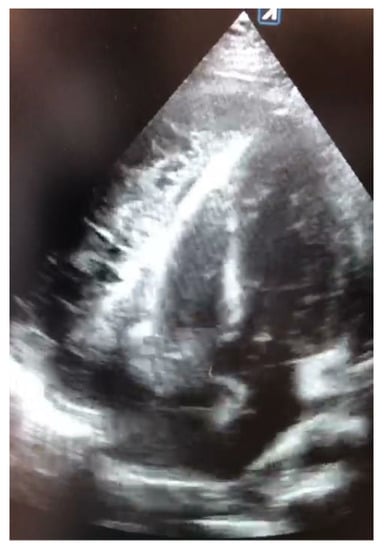

Total-body contrast-enhanced computed tomography (CT) was performed, which showed large pericardial effusion with hyperemia of the pericardial layers, associated with moderate bilateral pleural effusion, more significant on the left side (Figure 2).

Figure 2. Contrast enhanced in thoracic CT. Severe pericardial effusion and left pleural effusion were observed.